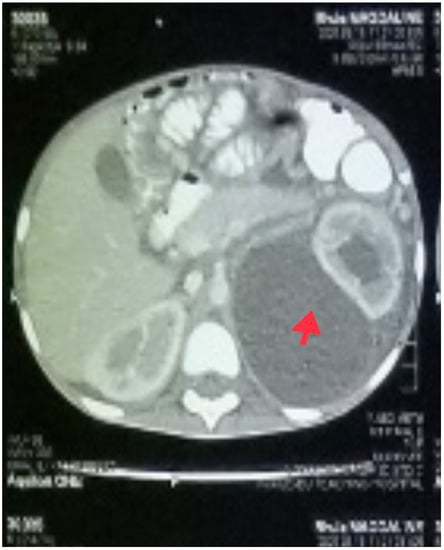

In addition to starting broad-spectrum antibiotics (IV ceftriaxone 1 g daily and vancomycin 40 mg/kg daily) for suspicion of bacteria coinfection and IV electrolyte replacement and fluid resuscitation with normal saline infusion, an abdominal CT scan was performed, which revealed a large cystic mass (possibly a urinoma) on the left kidney with hydronephrosis and moderate ascites (Figure 3).

Figure 3. A cross-sectional view of the abdominal CT scan showing large left renal cyst (red arrow) with hydronephrosis.